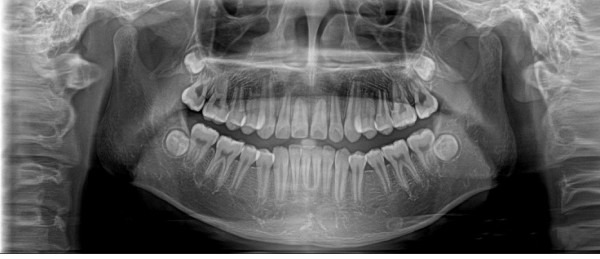

全景机基于体层摄影原理设计而成,全景摄影时,根据口腔颌面部的解剖特点,X线球管围绕人体头部选择约120°,从一侧颞下颌关节到另一侧颞下颌关节,最后一次性获得全口牙齿的2D图像,使颌骨及全口牙体层摄影在一幅图片上呈现左右展开的平面图。

全景机具有观察全面、操作简便、儿童及老弱患者容易接受的优点。然而,全景机的缺点也非常明显:

1.相较牙片机,全景成像中牙齿内部的清晰度和细节明显要略逊一筹;

2.由于是曲线体层成像,其图像有比较严重的畸变失真,同样也不可避免的具有影像重叠。

因此,全景机主要用于观察所有牙齿的形态、位置及颌骨内情况,为牙齿正畸矫正、牙齿修复提供图像依据,不太适合用于对牙齿结构成像清晰度要求非常高的领域。